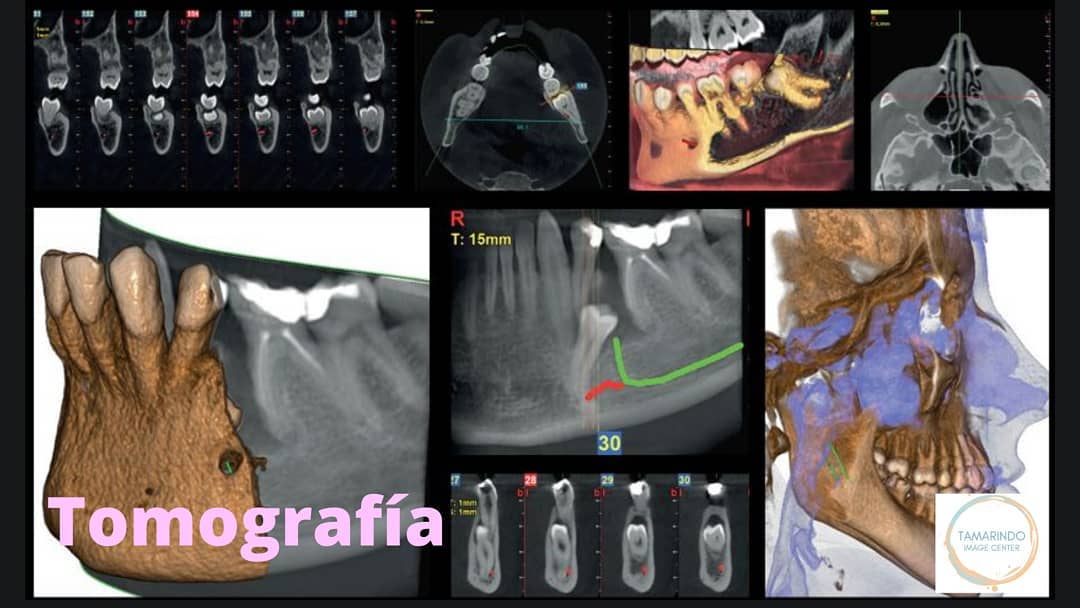

Tamarindo Image Center is a modern 3D radiology facility dedicated to supporting dental professionals in delivering safer, more precise treatments. Located in the Tamarindo area, the center is equipped with a state-of-the-art Cone Beam Computed Tomography (CBCT) scanner, capable of capturing both 3D and 2D diagnostic images with exceptional accuracy and clarity. This advanced technology allows dentists to plan treatments with confidence, ensuring better outcomes for their patients.

By offering high-quality imaging services, Tamarindo Image Center plays a vital role in enhancing diagnostic capabilities across a wide range of dental specialties. CBCT imaging provides detailed views of bone structure, nerve pathways, and surrounding anatomical features—information essential for procedures such as dental implant planning, orthodontics, endodontics, oral surgery, and complex restorative cases. The center’s precise imaging helps reduce risk, improve treatment predictability, and support minimally invasive approaches.